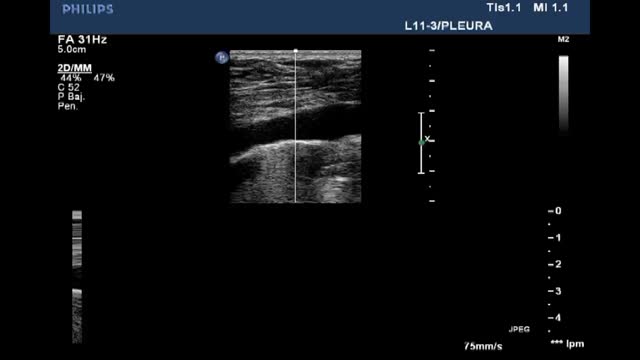

A high-frequency linear probe is used for this measurement, positioned at the last intercostal spaces (we place the probe on the anterior axillary line, generally perpendicular to intercostal spaces 7-8, 8-9 and 9-10, with the probe covering two ribs in order to visualize the diaphragm apposition zone)(Suppl. Fig. 13), ideally with the patient in the supine position. A somewhat more posterior position of the probe has also been described, between the anterior and mid-axillary lines. In this way, we locate the “apposition zone” where the diaphragm inserts into the chest wall. The diaphragm is identified as a hypoechoic band delimited by two hyperechoic lines corresponding to the pleura and peritoneum (Suppl. Fig. 14).22,31–35